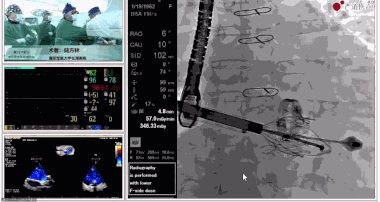

▲瓣膜植入前右心室造影

▲瓣膜植入過(guò)程

在手術(shù)直播中瓣膜植入過(guò)程不到10分鐘,手術(shù)獲得圓滿(mǎn)成功,充分體現(xiàn)徐志云、陸方林團(tuán)隊(duì)技術(shù)精湛,團(tuán)隊(duì)協(xié)作默契及器械的優(yōu)越性。